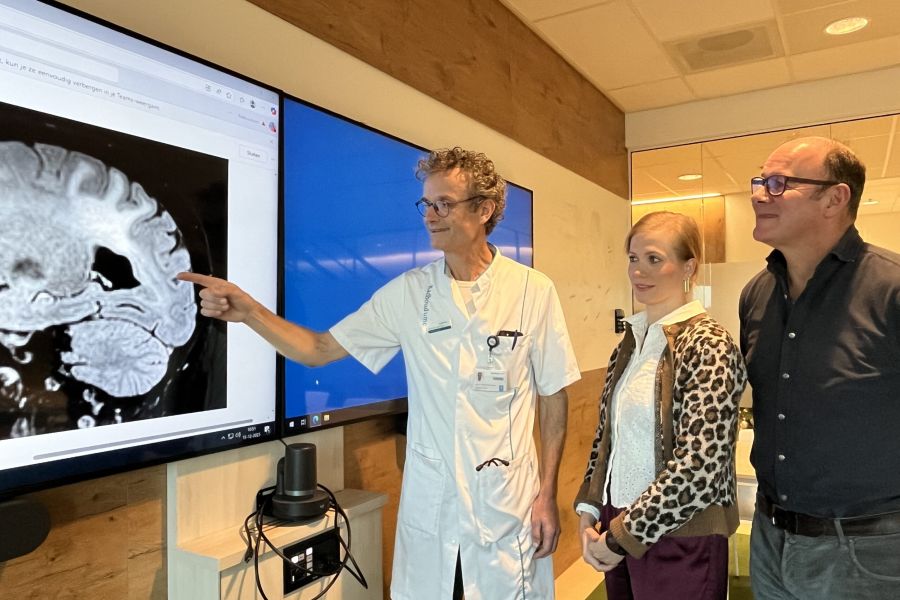

Catharina Ziekenhuis erkend als Topklinisch Expertisecentrum voor herseninfarct op jonge leeftijd

Als een jonge vrouw of man een herseninfarct krijgt, staat het leven ineens stil. Juist voor deze patiënten heeft het Catharina Ziekenhuis nu een STZ-erkenning als Topklinisch Expertisecentrum voor Young Stroke gekregen. Een herseninfarct wordt vaak gezien als iets dat vooral oudere mensen overkomt. Toch krijgen ook jongere volwassenen ermee te maken. En voor hen zijn de […]

Veel jonge mensen houden cognitieve klachten na een herseninfarct

Denkproblemen blijven vaak bestaan en beïnvloeden het werkzame leven Cognitieve problemen komen vaak voor bij jonge mensen die een herseninfarct hebben gehad. Deze klachten houden bij een groot deel van hen langdurig aan. Het gaat onder meer om een tragere informatieverwerking, taalproblemen en geheugenstoornissen. Bij ernstige cognitieve klachten neemt bovendien het risico op werkloosheid toe. […]